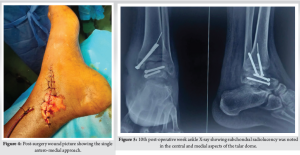

Case Report: We share this unusual case of a Hawkins type-3 talus neck fracture along with a serious Grade 3B medial malleolus fracture and ankle subluxation, which was treated with cleaning the wound, realigning the ankle, and surgery to fix the bones. Post-operatively, the wound was healthy and free of infection. Despite being told to avoid weight-bearing for three months, the patient lost follow-up after a month and started occasional partial weight bearing. During the 10th post-operative week, we found a mild degree of talar neck collapse and Hawkins sign radiologically. The range of motion for the ankle was dorsiflexion of 0–15° and plantar flexion of 0–30°, with minimal swelling and pain on weight bearing.

The combination of talar neck fracture and ankle subluxation, along with ipsilateral medial malleolar fracture, is exceptionally rare. Very few cases have been reported until now [4,5]. Numerous reports have been made of complications, such as osteonecrosis, collapse, malunion, post-traumatic arthritis, and discomfort [3]. The time of definitive fixation depends on multiple factors, including fracture comminution and subtalar dislocation/subluxation [6,7]. Talus fractures that happen with a malleolar fracture have a lower chance of avascular necrosis (AVN) because the ligament-capsule complex between the broken piece and malleolus is still intact, which helps keep the blood supply and soft tissue healthy. In our case, we operated on an emergency basis within 10 h of injury due to associated fracture comminution, open soft tissue injury, and unreduced ankle subluxation to minimize the risk of future avascular necrosis. A retained broken guide wire during medial malleolus fixation was decided not to remove given its harmless intramedullary position and to prevent the further soft tissue damage that will incur during the extraction process that will increase the overall operative time and chances of infection. Although asymptomatic, this intraoperative event underscores the need for caution during hardware placement and raises potential concerns for future procedures. Post-operative x-rays revealed a partial Hawkins sign in the central and medial region of the talar dome, which is reliable evidence of talus vascularity after fracture and suggests that the chances of AVN are unlikely [8,9]. Our case was managed without CT or MRI, which the patient declined given the patient’s poor socio-economic status. While this limited detailed fracture assessment, it emphasizes the role of clinical judgment and standard radiographs in urgent surgical decision-making when advanced imaging is unavailable. The present standard for treating talus neck fractures is to use the anteromedial and anterolateral dual incision techniques [6]. In our case, we used the open medial wound proximally and extended the incision anteromedially and distally. Open fractures, which are frequently accompanied by soft tissue contamination and stripping, were discovered to have a 25% deep infection risk in open talus injuries [10]. The emergency reduction of dislocation, limb elevation, appropriate antibiotic administration, and tension-free suturing of the wound can all help to reduce soft tissue and wound problems, such as skin necrosis, infections, and poor wound healing [6]. Our patient showed no signs of a superficial or deep surgical site infection after surgery. While the single anteromedial approach was effective in our case, further randomised comparative studies with standard dual-incision techniques will be required to study the relative benefits or limitations of this approach. Several studies [6] have found a correlation between poor functional results and increasing injury severity. Although our patient lost contact after a month and began intermittent partial weight-bearing, the patient had better functional results. Talar neck malunion rates can range from 20% to 37%, while talar neck nonunion rates are uncommon (5% each) [7]. On the X-ray taken in the 10th week following surgery, there was no sign of talar neck malunion in our case. Despite instructions for strict non-weight bearing, the patient began early partial weight bearing. This sub-optimal compliance is explained by the poor socioeconomic status, cultural belief, long travel distance from their rural area to the hospital etc. This introduces a variable in outcome interpretation and underscores the importance of understanting the patient’s socio-economic condition. Post-traumatic subtalar arthritis is a typical long-term complication in such cases [7]. Our case requires a long-term follow-up since post-traumatic arthritis progresses over time. Our patient discontinued follow-up after one month, returning only at the 10th week yet presented with good clinical and functional outcome given the complexity of the case presentation. This highlights the challenges of ensuring long-term monitoring in trauma cases, especially in socioeconomically constrained populations.